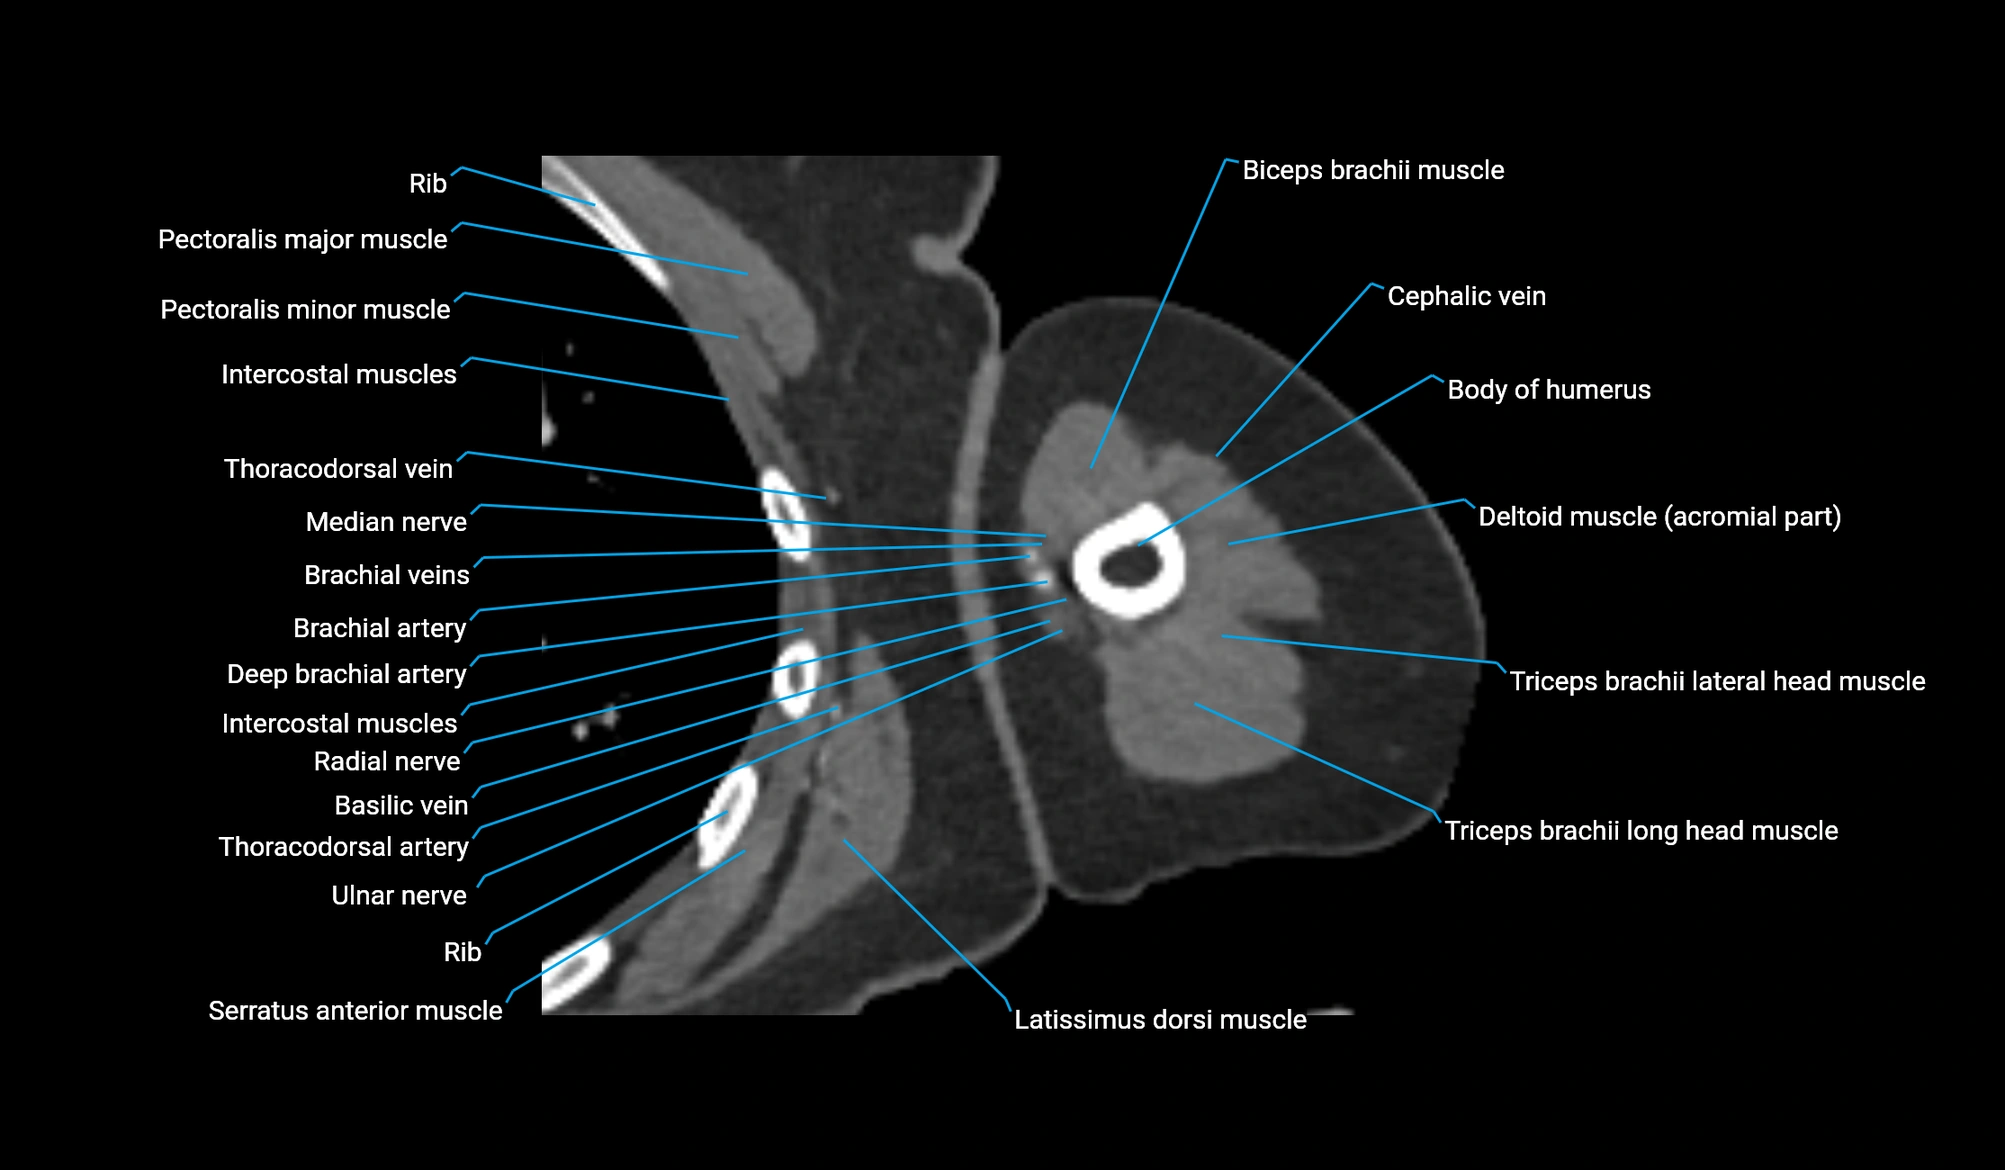

CT image